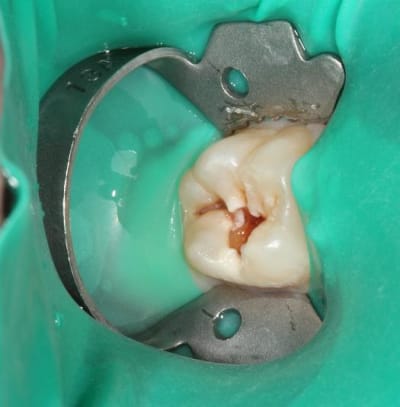

Quelques photos pour illustrer le sujet initial. Dommage que ces dents n'aient jamais eu de sealants.

Pour l'effraction pulpaire sur dent asymptomatique, je fais le protocole que Choixpeau avait mis sur le forum : hypochlorite puis adhésif directement au contact. Aucun problème à court terme pour le moment.

Si effraction plus importante : MTA.